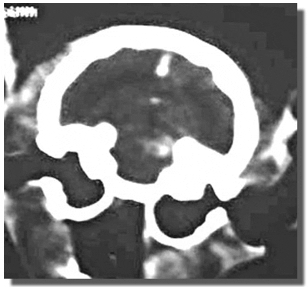

Figura 7-A: Gato adulto con síndrome vestibular central. Nótese la desviación de la cabeza y cuello hacia el lado derecho, y la tetraparesia. El animal presentaba deficiencias propioceptivas en los miembros del lado izquierdo, es decir, el lado opuesto a la inclinación cefálica (síndrome vestibular paradóljico)

Figura 7-B: TAC del gato antetrior. Obsérvese la masa tumoral en el cerebelo, del lado izquierdo.